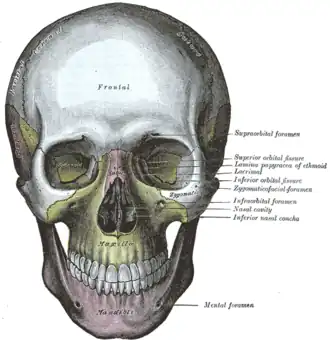

Фронтальный вид. Верхняя челюсть в центре, обозначена жёлтым. | |

У человека воздухоносная, так как в ней находится обширная полость — верхнечелюстная (гайморова) пазуха (sinus maxillaris). Имеет тело верхней челюсти (corpus maxillae), 4 отростка: лобный отросток (processus frontalis), альвеолярный отросток (processus alveolaris), небный отросток (processus palatinus), скуловой отросток (processus zygomaticus). Поверхности верхней челюсти: передняя поверхность (facies anterior), носовая поверхность (facies nasalis), подвисочная поверхность (facies infratemporalis), глазничная поверхность (facies orbitalis)[1].

- подглазничная борозда (sulcus infraorbitalis);

- подглазничный канал (canalis infraorbitalis);

- подглазничное отверстие (foramen infraorbitalis);

- подглазничное отверстие (foramen infraorbitale);